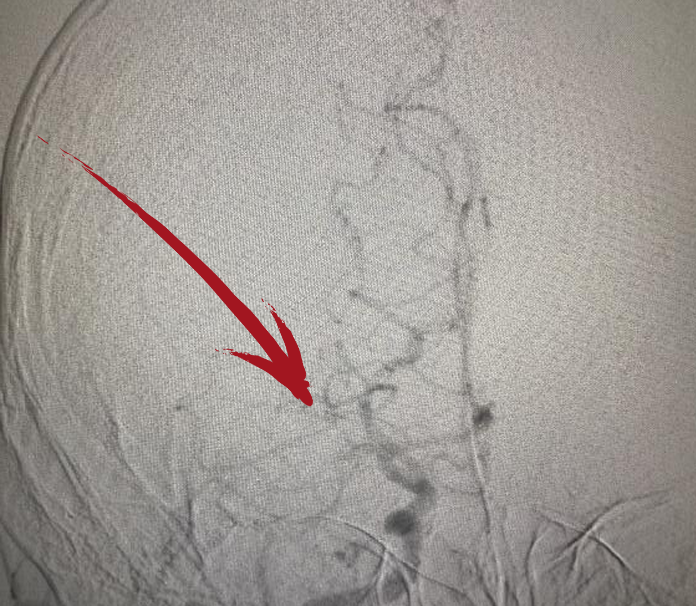

▲术前DSA右侧大脑中动脉起始段闭塞

▲术后DSA提示右侧大脑中动脉已开通